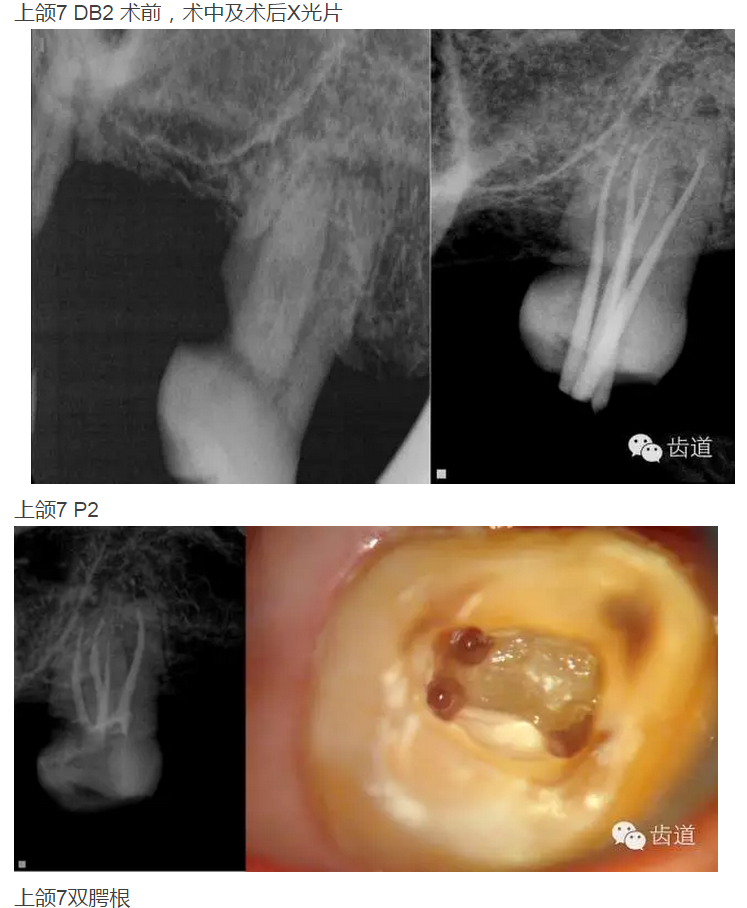

上頜第二磨牙:與上頜第一磨牙相似,多為3根管,偶見雙鄂根管;